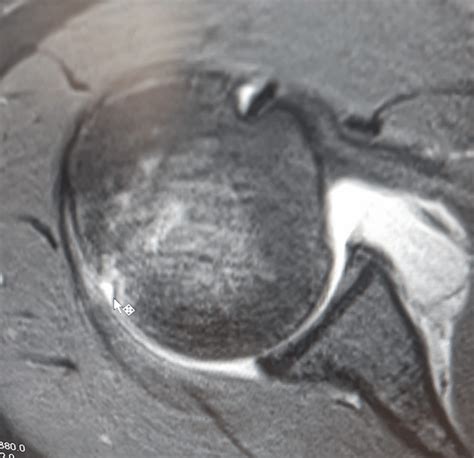

MRI or MR Arthrogram Used to evaluate the soft tissues, specifically the labrum and surrounding ligaments.

💡 Note: While a CT scan is highly accurate for bony defects, a surgeon will almost always order an MRI to assess associated soft tissue injuries like a Bankart tear, which frequently accompanies a Hill-Sachs lesion.